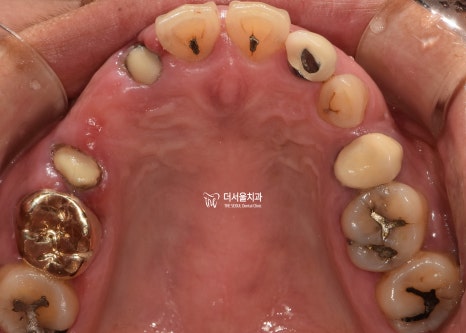

무절개로 방향을 잡고

컴퓨터 분석을 이용해

식립 위치를 결정하고

어떤 형태로 올라갈 것인지

디자인 과정까지 끝마쳤습니다.

텅 비어져 있던 곳이

튼튼한 임플란트로 채워져 있네요.